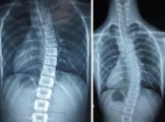

• 医疗人工智能|我国科学家全球首创脊柱侧弯大规模人工智能筛查系统 6年前

该智能系统的筛查准确率已经达到了人类专家平均水平,且速度要明显优于人工。

人工智能 人工智能筛查 脊柱侧弯